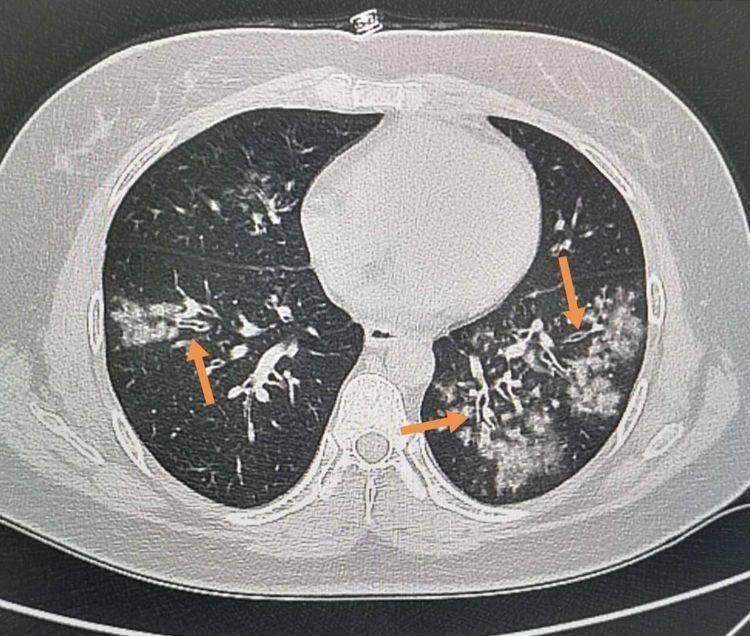

摘要:冠状毒肺炎持续全球蔓延,最新消息显示疫情形势依然严峻。全球各国积极应对,加强防控措施,并开展疫苗研发和临床治疗。目前,全球疫情动态表现为多点散发与局部爆发并存,需要全球协作共同应对。应对策略主要包括加强疫情监测和预警,提高检测能力和隔离治疗水平,推广预防措施,加强国际合作和信息共享。

截至最新数据,冠状毒肺炎已在全球范围内造成大量感染病例和死亡病例,疫情在全球范围内呈现出不同程度的爆发态势,各国政府纷纷采取紧急措施以遏制疫情传播,目前,一些国家疫情已得到初步控制,但仍有部分国家和地区面临严峻挑战。